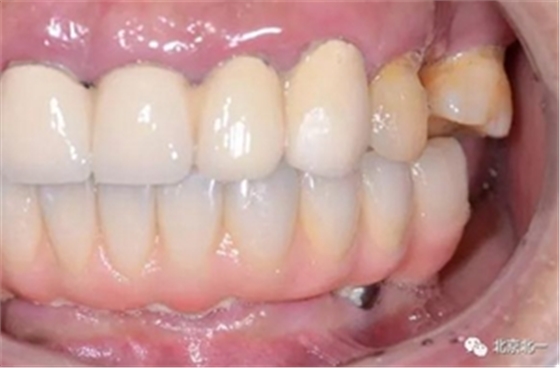

圖二十四:2017年11月復(fù)查時照片,植體很穩(wěn)定, 無骨吸收。

圖二十五:口內(nèi)照。